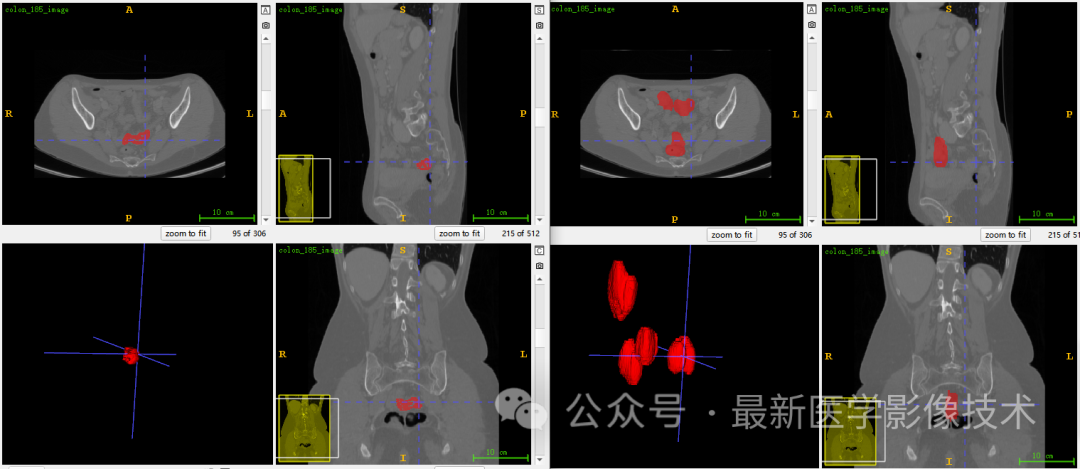

5、验证集分割结果

左图是金标准结果,右图是预测结果。